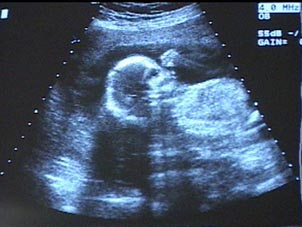

A documentary that addresses current issues in childbirth.